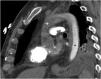

A 56-year-old man presented with profound shock and unresponsive hypoxemia. Pulmonary embolism was suspected given the extremely dilated right ventricle with septal flattening. It was decided then to start peripheral veno-arterial extracorporeal membrane oxygenation (VA-ECMO) through bedside cannulation. 72h later, the patient was on unfractionated heparin, had recovered from multiorgan failure without neurological impairment and vasopressors had been withdrawn. However, persistent hypoxemia and right ventricle dysfunction challenged ECMO weaning. A computed tomography confirmed the diagnosis (Fig. 1) and provided evidence of the harlequin syndrome (Fig. 2) as the two bloodstreams, the native cardiac output and oxygenated ECMO return, meet in the watershed area. Subsequently, the patient underwent a successful transcatheter pulmonary thromboaspiration (Fig. 3) and could be weaned from mechanical ventilation and ECMO the following days. He was discharged two weeks later without further complications.